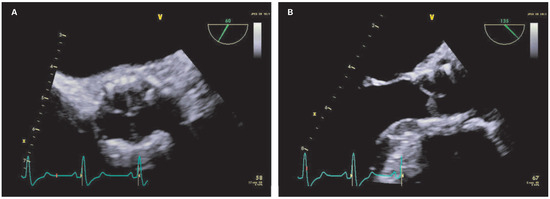

Case report